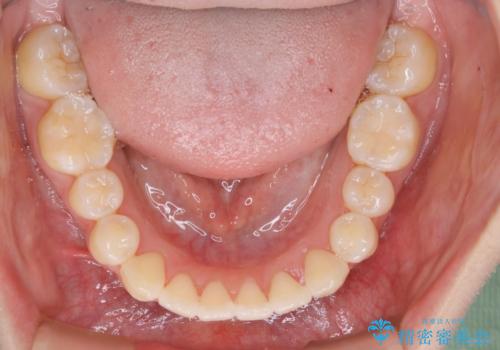

矯正装置の希望がインビザラインだったため、マイクロインプラントを併用し、奥歯から順に遠心移動をかけていくことにより非抜歯でも主訴のガタつきを治すことができました。

術前・術後の笑った時の歯の見え方の変化にも注目してみてください!

マウスピースとマイクロインプラントを組み合わせることで、抜歯をしなくても歯並びを治すためのスペースを作ることができます。奥歯から順に移動させていくので前歯に変化が出るまでには時間がかかりますが、その分健康な歯を抜歯することなく理想的な歯並びを手に入れることができます。